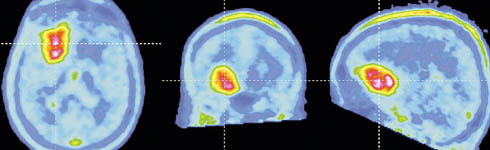

Positron Emission Tomography (PET)

The PET Scan is the latest engineering breakthrough in imaging technology and an important supplement to CT Scanning and MRI. PET technology allows doctors to observe cellular-level metabolic changes with powerful cross-section images of the body. PET Scans are now used to detect some cancers, coronary heart disease and brain disorders.